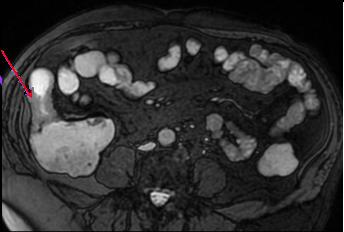

Portion stenosant de ileon avec

epaissisement de la paroi . Dilatation de l'intestin

en amont peut se voyait ( fleche rouge ) .

Image IRM en coupe axiale |

"Combs sign " de ileon :

Maladie de Crohn . Image IRM en coupe axiale . |